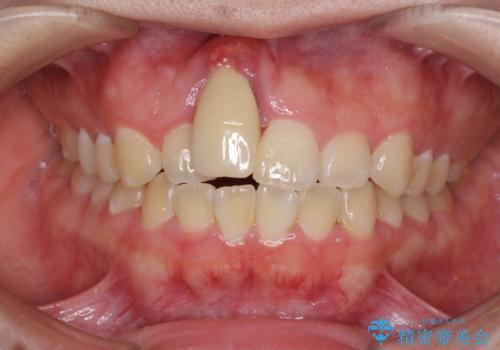

- 中学生の頃にぶつけた前歯に不格好なクラウンが装着されており、出っ歯な印象になっていることを気にして来院された患者様です。

ぶつけてしまった歯は保存が困難な状況であったので抜歯をし、ワイヤー矯正により歯列を整えつつ前歯の突出感を解消することとしました。

矯正治療後にはインプラント補綴治療を行うこととしました。

前歯の補綴治療はインプラントかブリッジかで悩んでいました。

周りの歯にむし歯がないため、インプラントがお勧めとなりますが、事故による骨欠損が大きく、歯肉ラインを整えるのが困難という問題がありました。